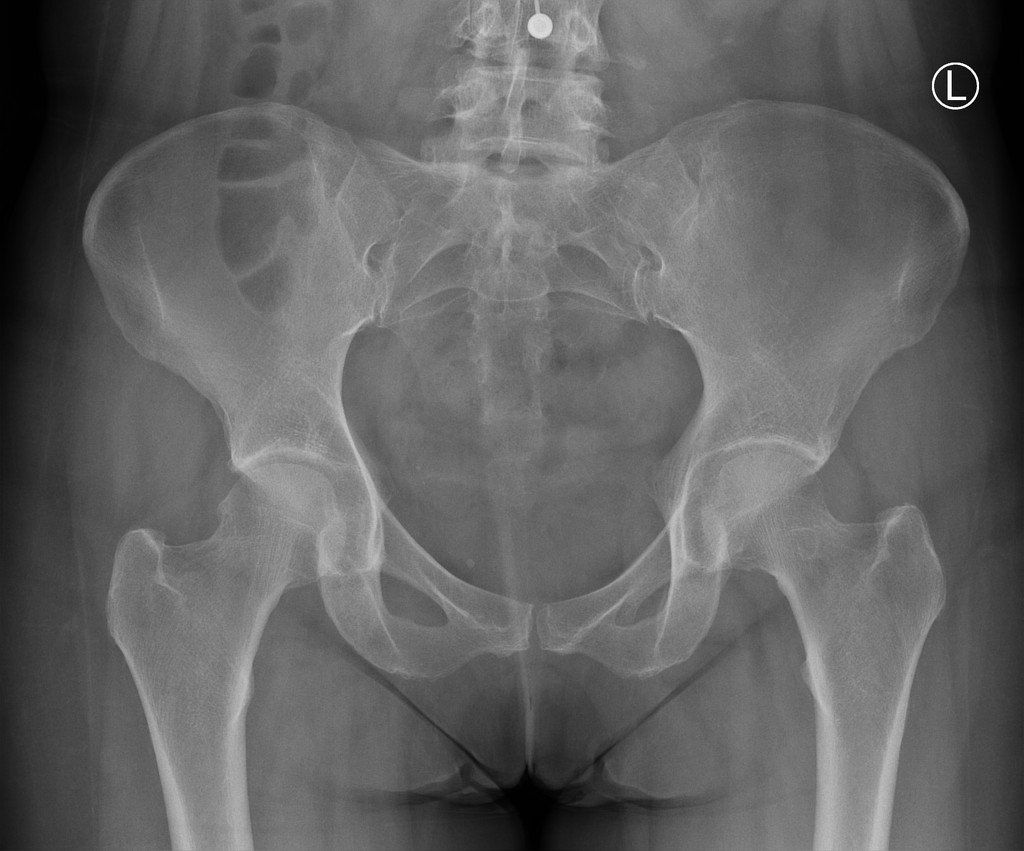

Diagnosis

The anatomy of the hip can be complex and it is important that a thorough objective assessment follows the subjective history taking. You will be asked to perform your provocative movements and activities as well as active and passively assessing the range of movement of your hip. This is important as other conditions which could mimic adductor related groin pain could be cam and pincer syndrome, inguinal hernia, iliopsoas bursitirs, neural compress, snapping hip syndrome or pain orginating from a visceral structure.